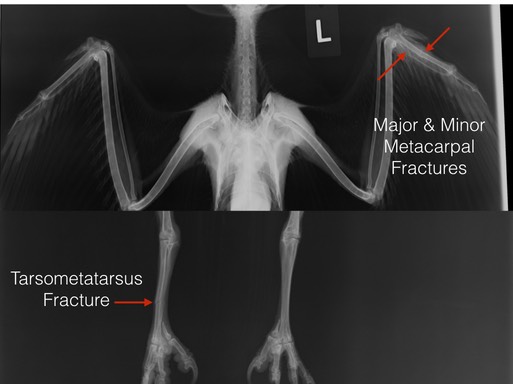

Swainson’s Hawk 18-483

We don’t know how this fledgling Swainson’s Hawk broke his left wing and right leg. He may have crashed into something while attempting to perfect his flying skills. We are hopeful that the fractures will heal quickly and both limbs will be fully functional.